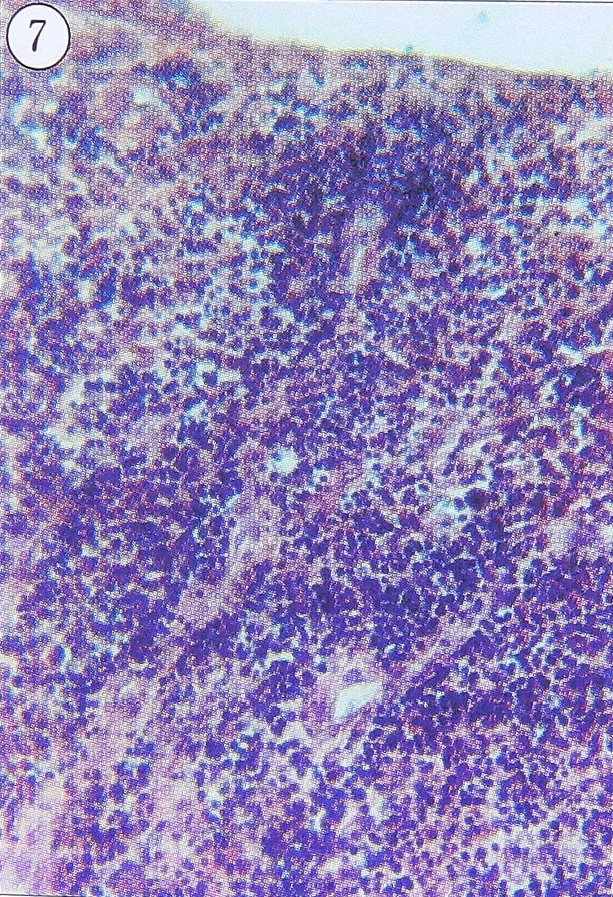

Рис. 7. Продуктивное воспаление высокой активности во внутренней оболочке капсулы очага при хроническом травматическом остеомиелите. Большеберцовая кость больного. Ув. 140.

- продуктивное воспаление высокой активности, с множеством интерстициальных сливающихся, диффузных мононуклеарно-плазмоцитарных инфильтратов (рис. 7);